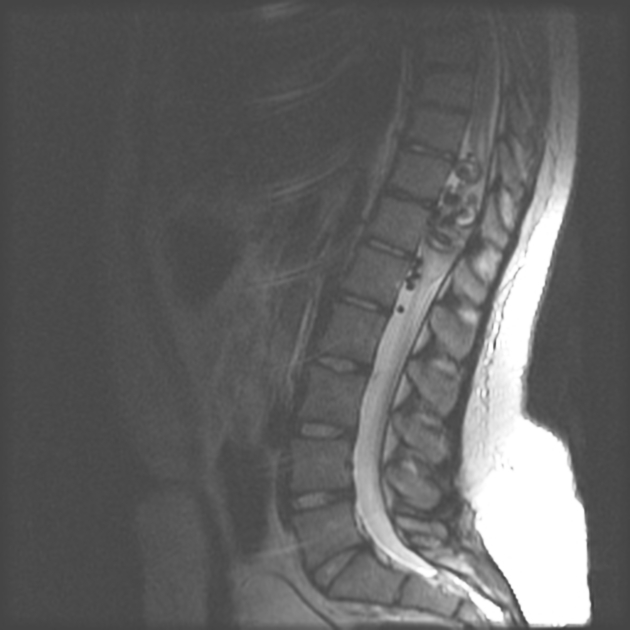

Spinal DAVF will have no flow voids in the cord itself, with have funky serpentine vessels surrounding the cord

notice the flow voids in the spiral cord. Spinal DAVF will have no flow voids in the cord itself, with have funky serpentine vessels surrounding the cord